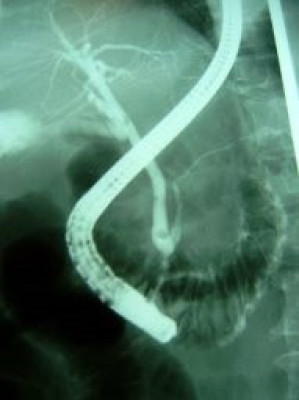

Coledocolitiasis pancreatitis biliar

Envíado por Dr. Carlos Miguel Zavaleta Consuegra